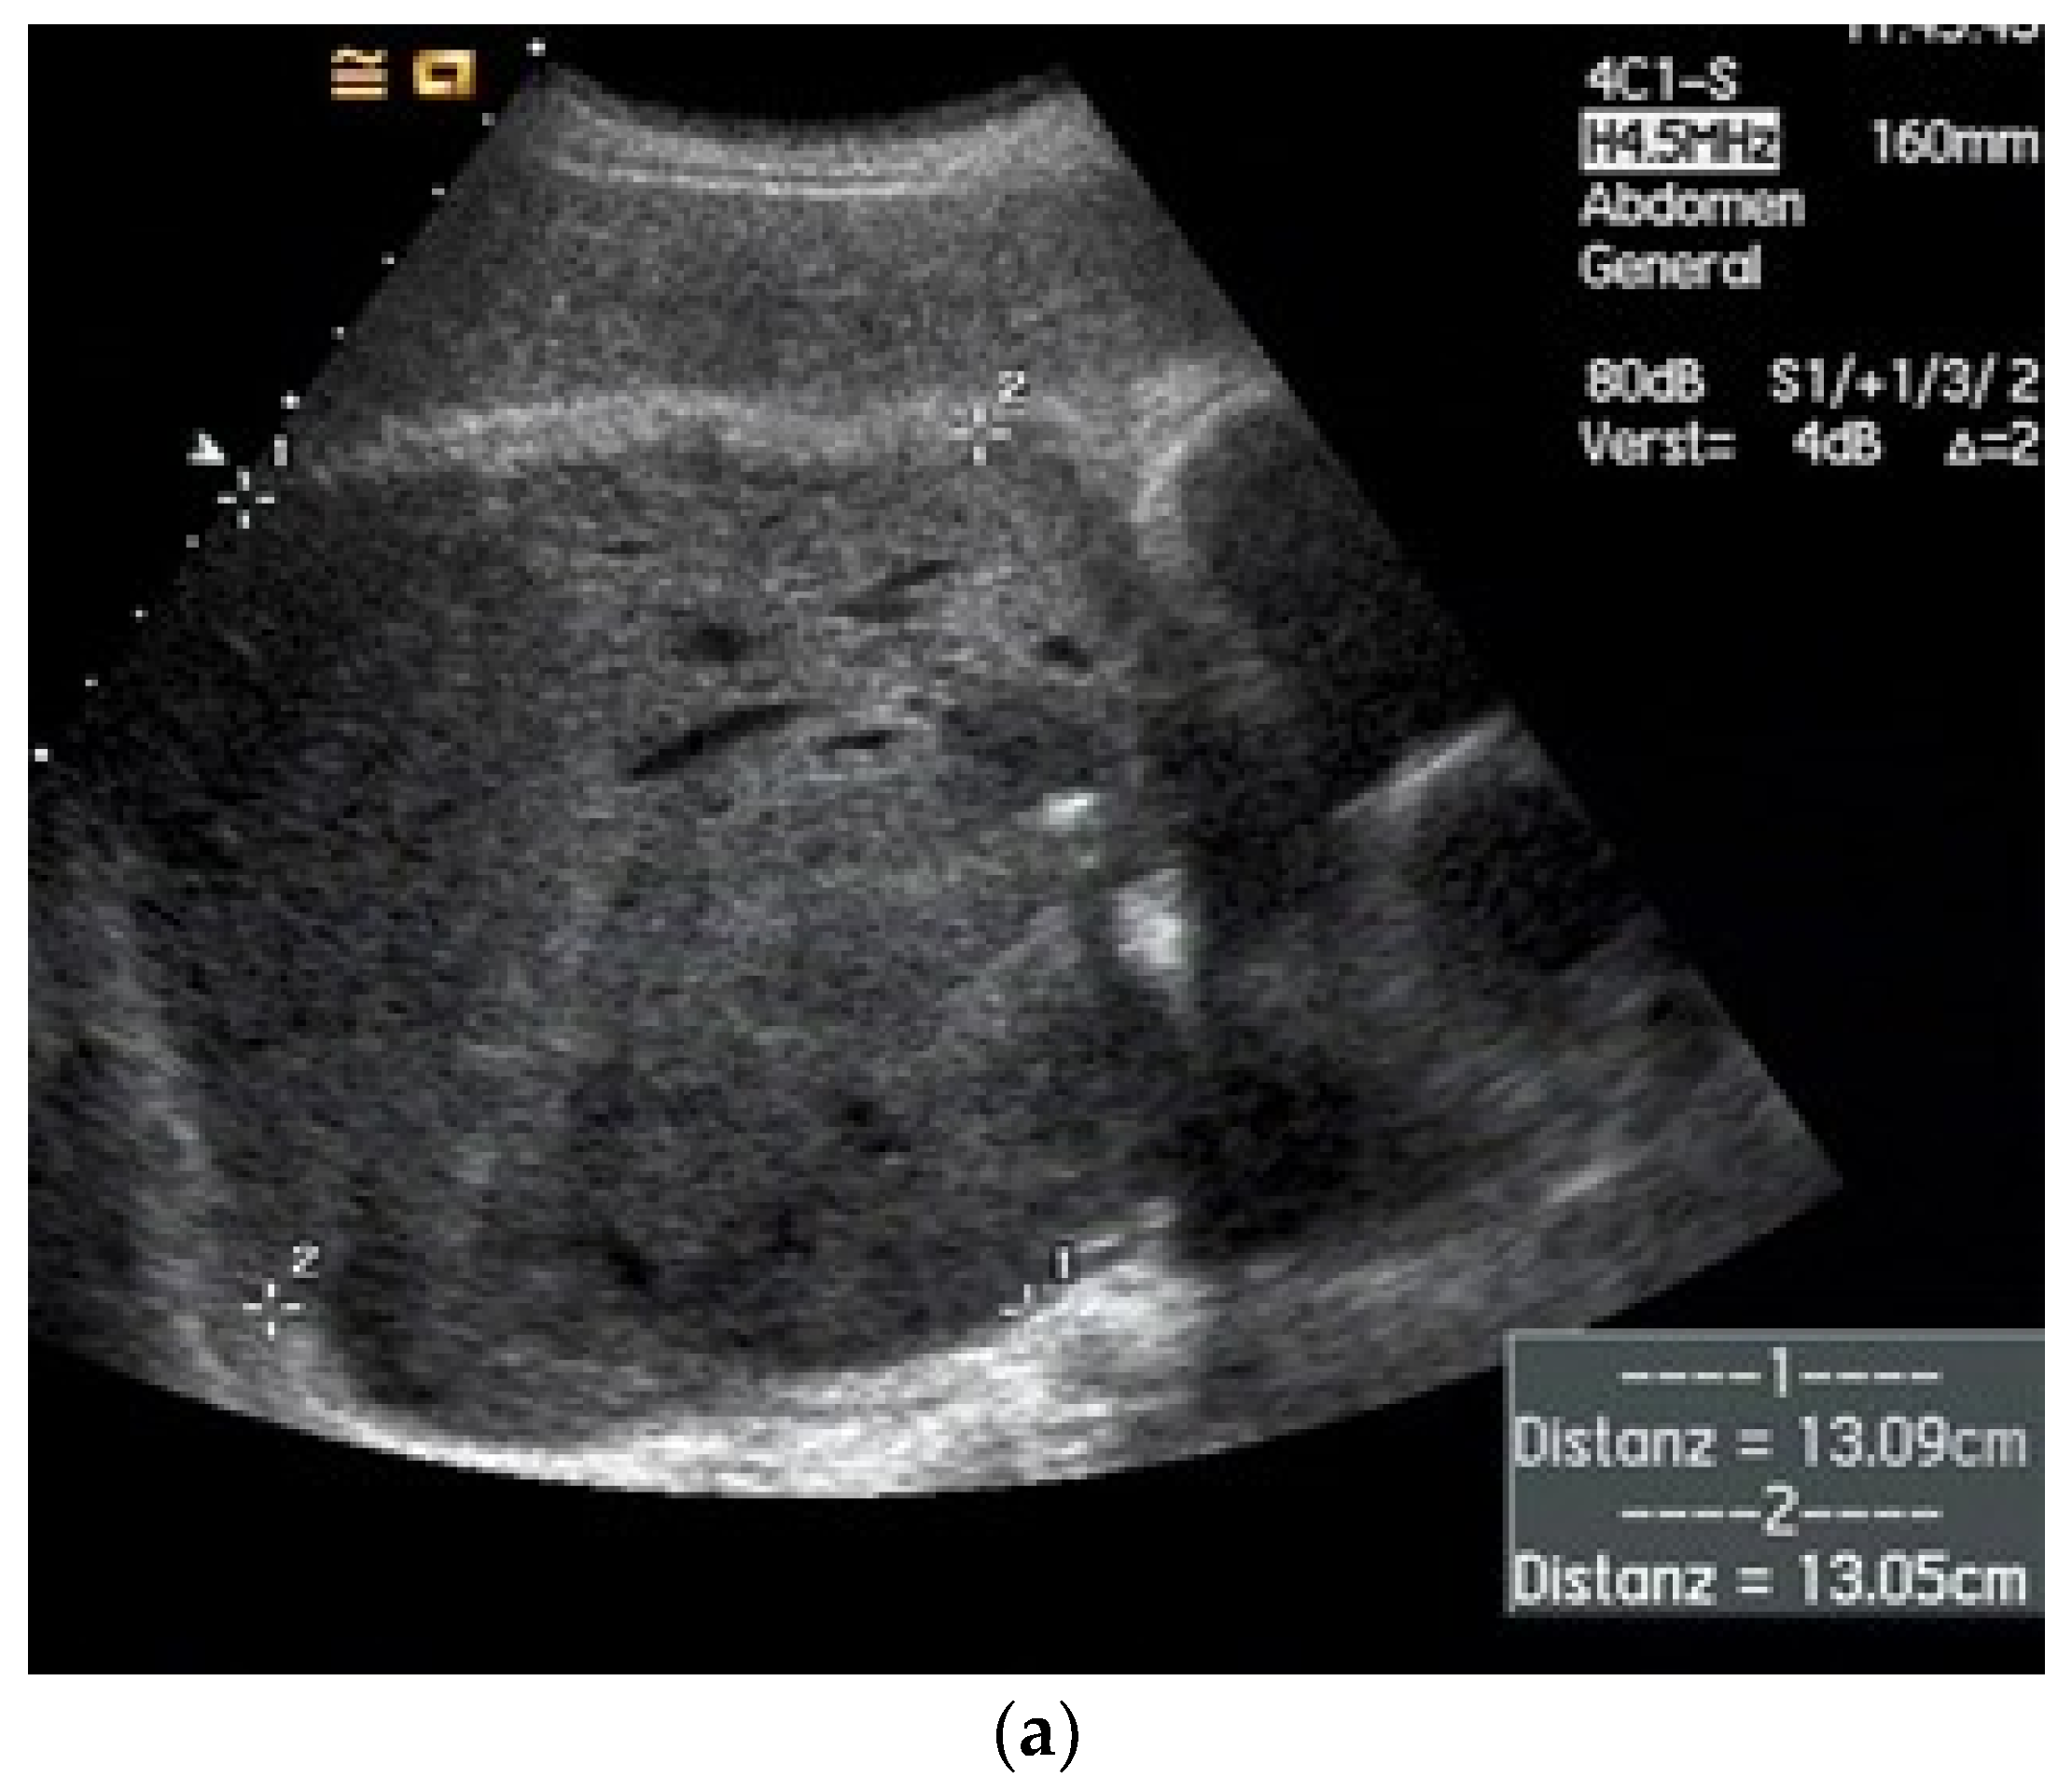

| Empyema | Hypoechoic thickened pleura, internal echos in the pleural effusion, hypoechoic pus, hyperechoic gas reflexes, fibrin strands, and chambering. In the phase of organization, thickened pleura, chambering of the pleural space. |

| Empyema necessitans | Exceeds the parietal pleura and infiltrates the surrounding soft tissue and chest wall muscles. |